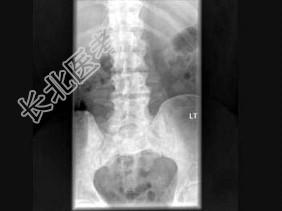

- 单项选择题男,77岁, 全身性骨痛,夜间加重, 贫血,PSA大于100, 结合图像,最可能的诊断是 ( )

A、成骨性骨转移

B、多发性骨髓瘤

C、慢性化脓性骨髓炎

D、骨肉瘤

E、以上都不是